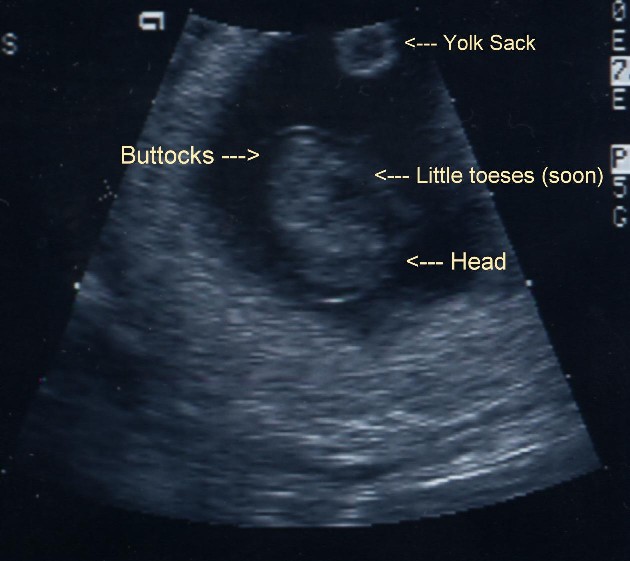

This is the ultrasound I had at 28 weeks. He sure got big in the past 20 weeks!